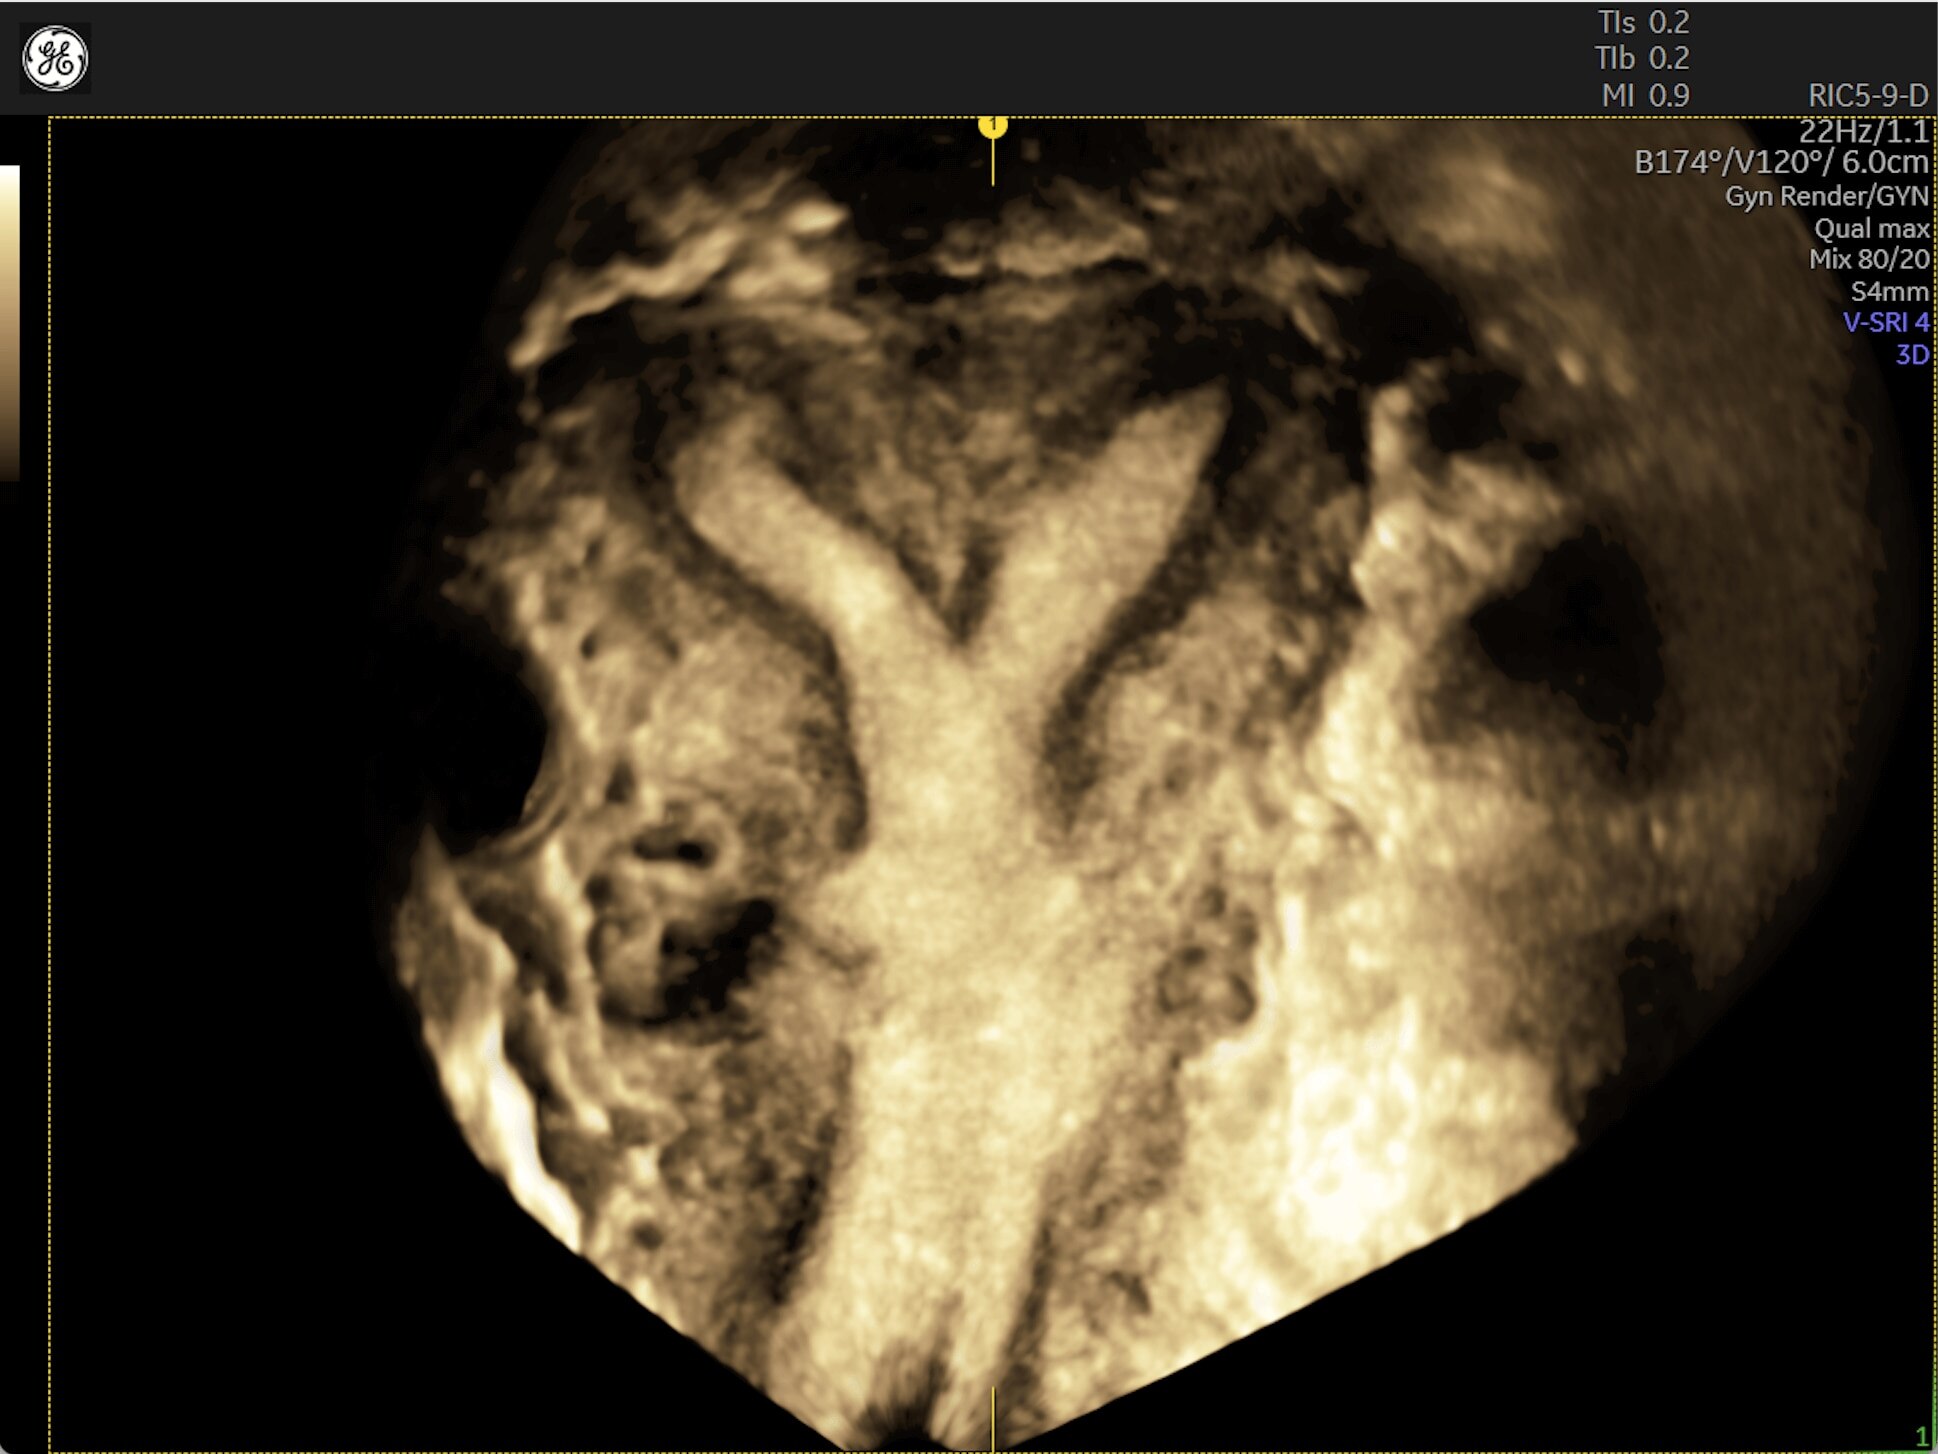

Generate spectacular 2D/3D and color Doppler images with increased penetration and stunning clarity, to help visualize critical details needed for diagnostic assurance. The Lyric Architecture unlocks new imaging and processing power to expand your imaging capabilities for years to come